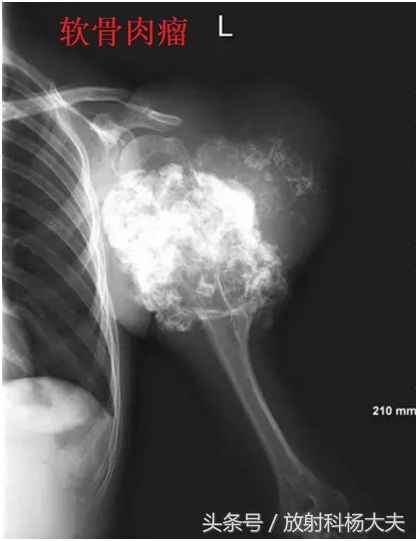

比如,下面的图,都是恶性的。

在骨关节的X线片上,通常在骨骼或骨骼边上看到这种高密度的类似骨骼一样东西,我们会考虑哪些?骨肉瘤,软骨肉瘤,创伤性骨炎,还有某些疾病引起的钙化,骨化等等。